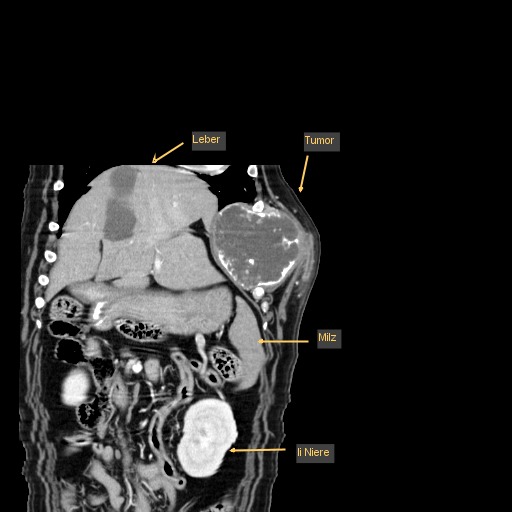

Leo wurde nun nach einer gründlichen allgemeinmedizinischen sowie labortechnischen Untersuchung zur Computertomographie (CT) angemeldet, die in Vollnarkose stattfinden muss. Mit dieser Technik werden mit Hilfe von Röntgenstrahlen ein Millimeter dünne Schichtaufnahmen angefertigt und damit das genaue Ausmaß des Tumors dargestellt. Zum anderen kann im Vergleich zu einem konventionellen Röntgenbild eine überlagerungsfreie Aussage über den Zustand des benachbarten Weichteilgewebes getroffen werden. Diese Informationen sind für den Chirurgen unumgänglich, damit er die Operation planen kann.

In diesem Fall wurde durch die CT das enorme Ausmaß der Umfangsvermehrung deutlich, sodass insgesamt drei Rippen inklusive der dazwischenliegenden Muskeln in Mitleidenschaft gezogen wurden. Die gute Nachricht war, dass der innerhalb der Bauchhöhle unmittelbar anliegende linke Leberlappen, Magen und Milz sowie der hintere Anteil des linken Lungenflügels im Brustkorb noch nicht vom Tumorwachstum erfasst waren.

Um eine Aussage für die Prognose hinsichtlich der Überlebenszeit des Patienten treffen zu können, die sich bei bösartigen Tumoren hauptsächlich vom Vorhandensein von Metastasen ergibt, wurde in der gleichen CT-Untersuchung die Brust- und Bauchhöhle von Leo mitgescannt. In der Lunge, den dem Tumor benachbarten Lymphknoten, sowie Leber und Milz setzen sich erfahrungsgemäß die frühesten Metastasen fest. Manche Besitzer wollen ihrem Liebling bei fortgeschrittener Tumorstreuung die Operation und etwaige langwierige Nachsorgebehandlungen ersparen. Bei diesem Patienten, der ja insgesamt in hervorragender körperlicher Verfassung war, konnten wir weder in der Brust- noch in der Bauchhöhle Metastasen feststellen, sodass einer operativen Entfernung des bösartigen Tumors nichts mehr im Wege stand.